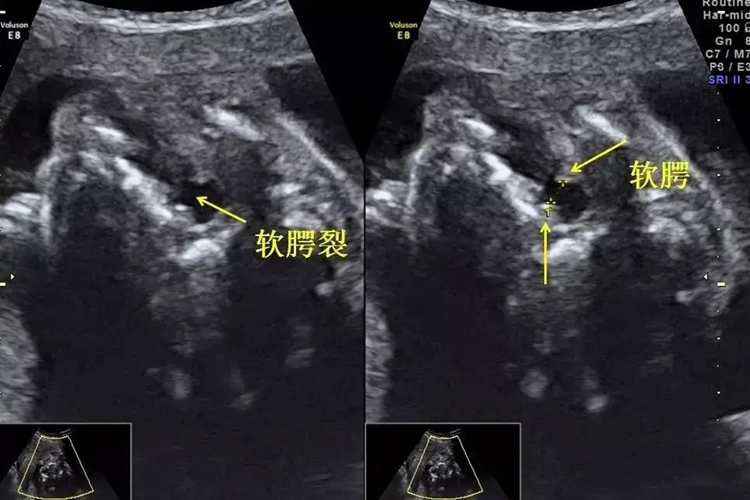

大排畸是在妊娠20-24周通过超声检查,判断胎儿是否存在脊柱椎弓间距增宽、软腭裂、心脏增宽等发育畸形情况。

大排畸通常在妊娠20-24周时进行的胎儿系统超声检查,筛查胎儿结构畸形。正常情况下胎儿心、脑、肾、膀胱、胃、上唇、四肢骨、脊柱、腹壁等均正常。当出现侧脑室增宽、脊柱椎弓间距增宽、软腭裂、双肾增大、心脏增宽、裂腹畸形伴肠管外翻等异常情况时,多提示胎儿发育异常。